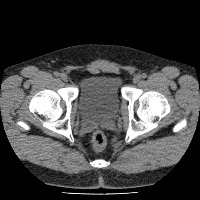

Regiao Renal

RegiaoRenal

regiao_renal